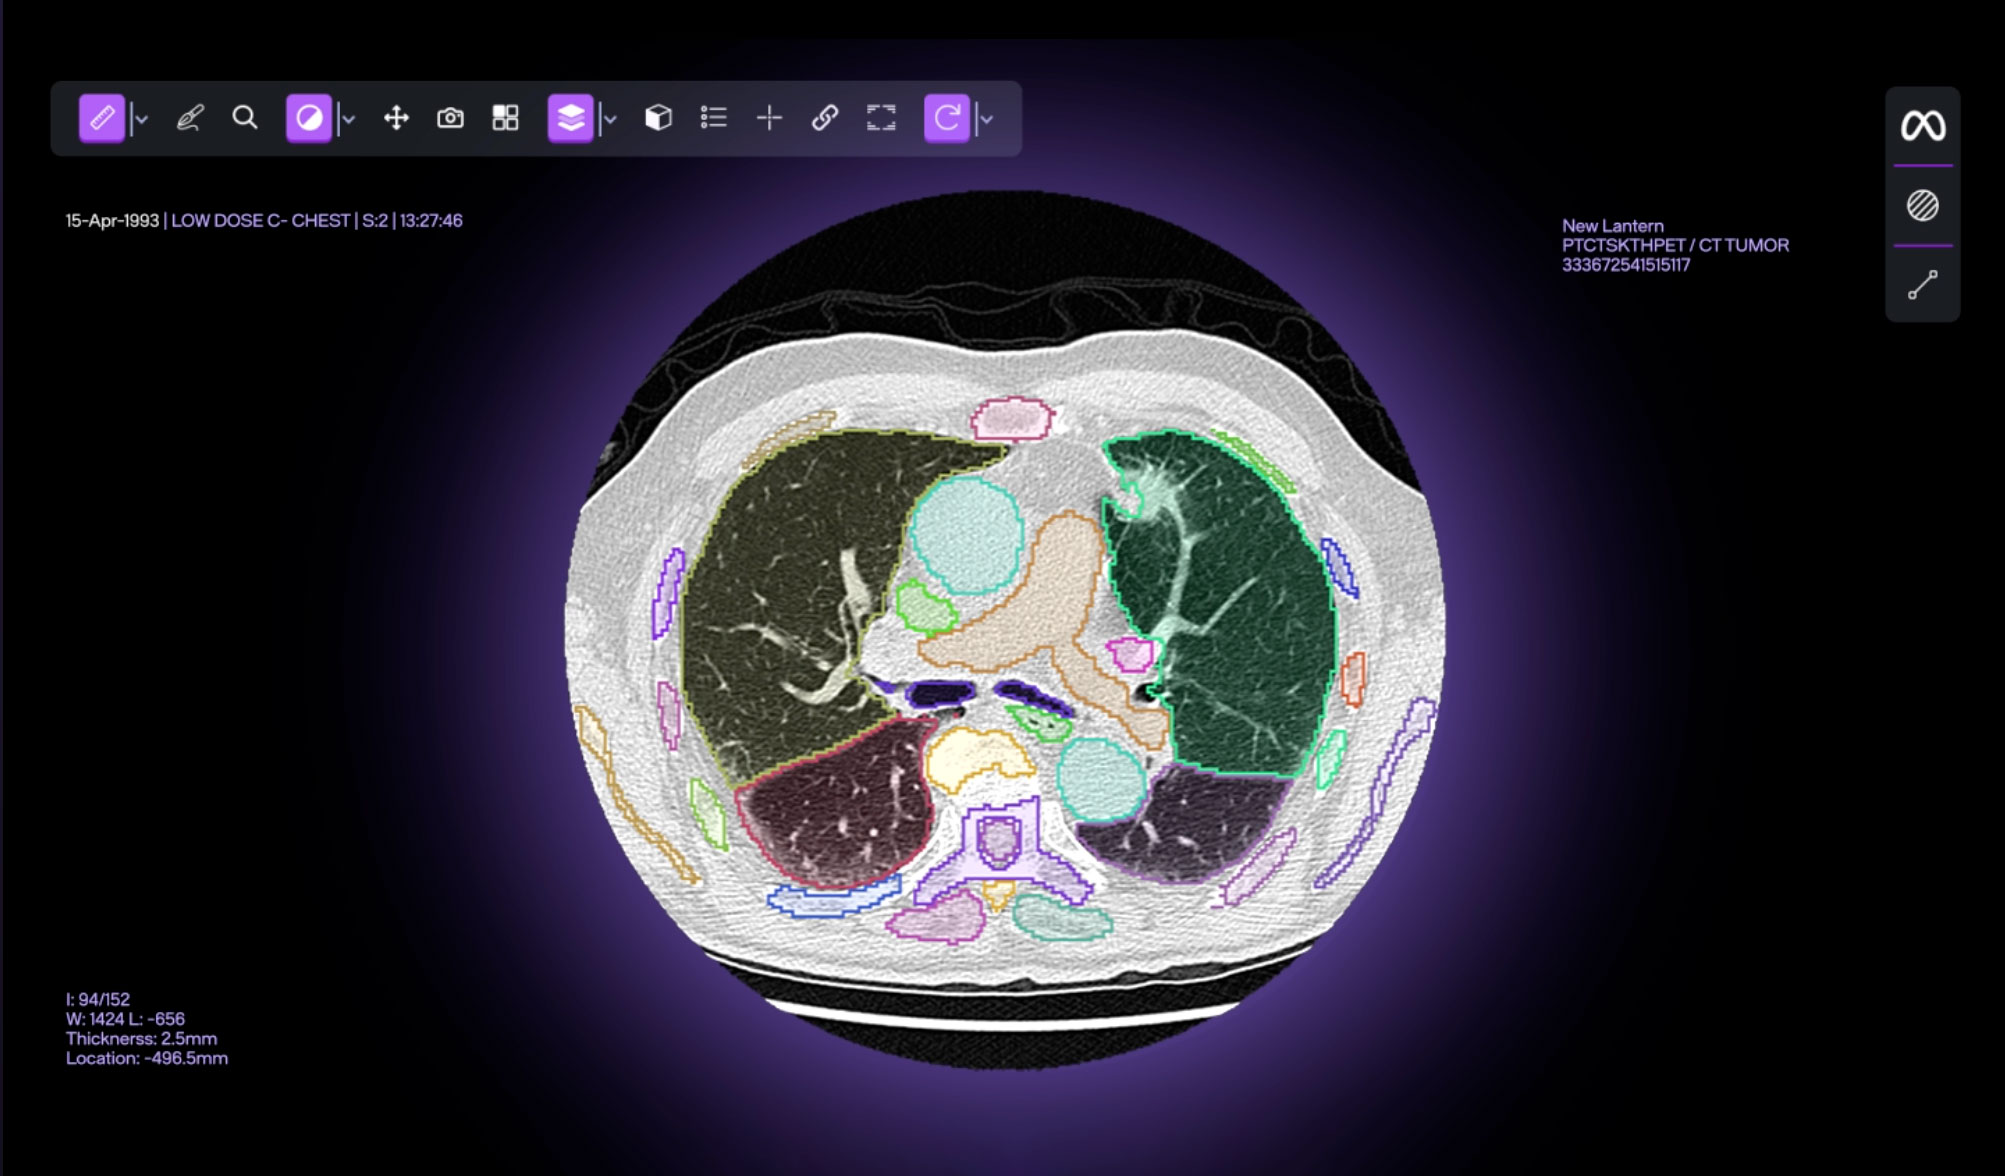

New Lantern accelerates radiology with cloud- and AI-powered medical image analysis.